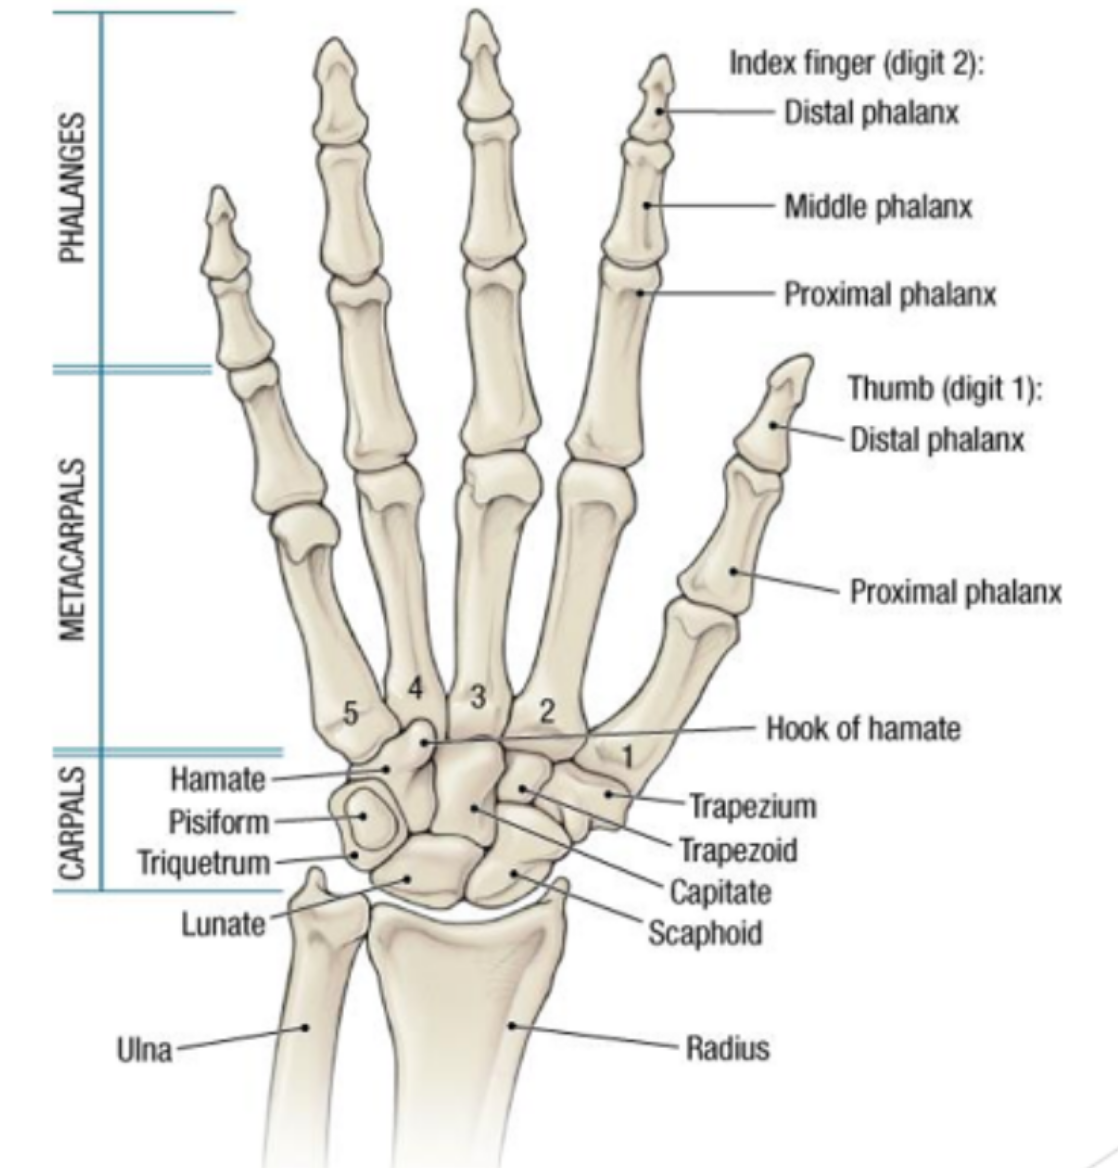

what are the three parts of the hand?

phalanges

metacarpals

carpals

What are the 3 divisions of the phalanges?

proximal, middle and distal

What are the fingers called? thumb?

digits and the thumb is called the pollex